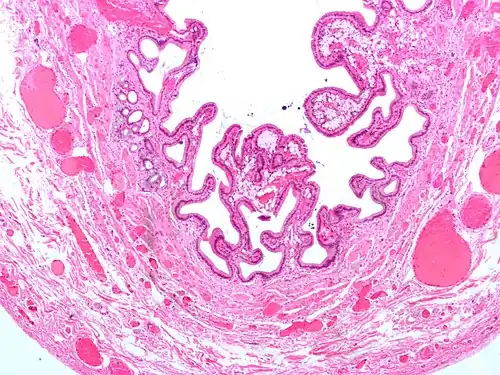

The name strawberry gallbladder comes from the typically stippled appearance of the mucosal surface on gross examination, which resembles a strawberry. The term was coined by surgical pathologist William C. MacCarty of the Mayo Clinic in 1910.[2] Cholesterolosis results from abnormal deposits of cholesterol esters in macrophages within the lamina propria (foam cells) and in mucosal epithelium. The gallbladder may be affected in a patchy localized form or in a diffuse form. The diffuse form macroscopically appears as a bright red mucosa with yellow mottling (due to lipid), hence the term strawberry gallbladder. It is not tied to cholelithiasis (gallstones) or cholecystitis (inflammation of the gallbladder).[3]

Additional images